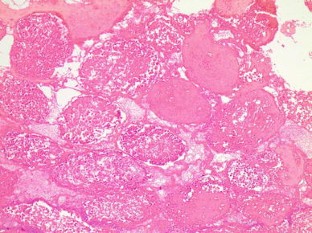

All rats in group A had normal testicular architecture (grade 1). The untreated group B had a mean grade of 3.81 (range 3.65–4). The treated groups C (mean grade 3.24; range 3.05–3.45) and D (2.69, range 2.4–2.9) presented statistically significant better results (lower grades) compared with the untreated group B. Group D had significantly better results (lower grades) than group C.

Fig. 1

Fig. 2

Fig. 3

Fig. 4

Fig. 5